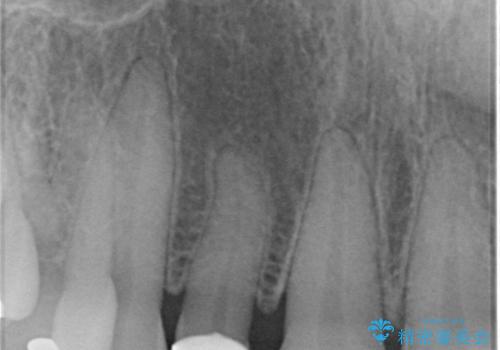

- 右上の2番目の前歯がとがった形をしていたため、セラミックで形を整えています。

下の前歯とのかみ合わせが切端咬合だったため、前歯の部分矯正も併せて行っています。(費用別途)